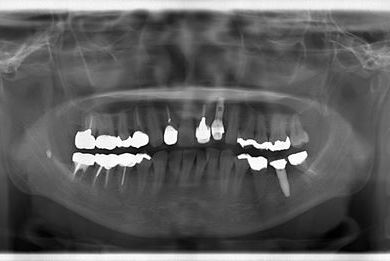

骨再生インプラント治療+セラミック治療

| 治療方針 | 骨再生法により、インプラント治療を可能にする。 | ||||||||||||||||||||||||||||||||

| 治療内容 | インプラント1本、メタルボンドセラミッククラウン2本、GBR | ||||||||||||||||||||||||||||||||

| 総治療費 | 618,660円 | ||||||||||||||||||||||||||||||||

| 治療期間 | 9ヶ月 |